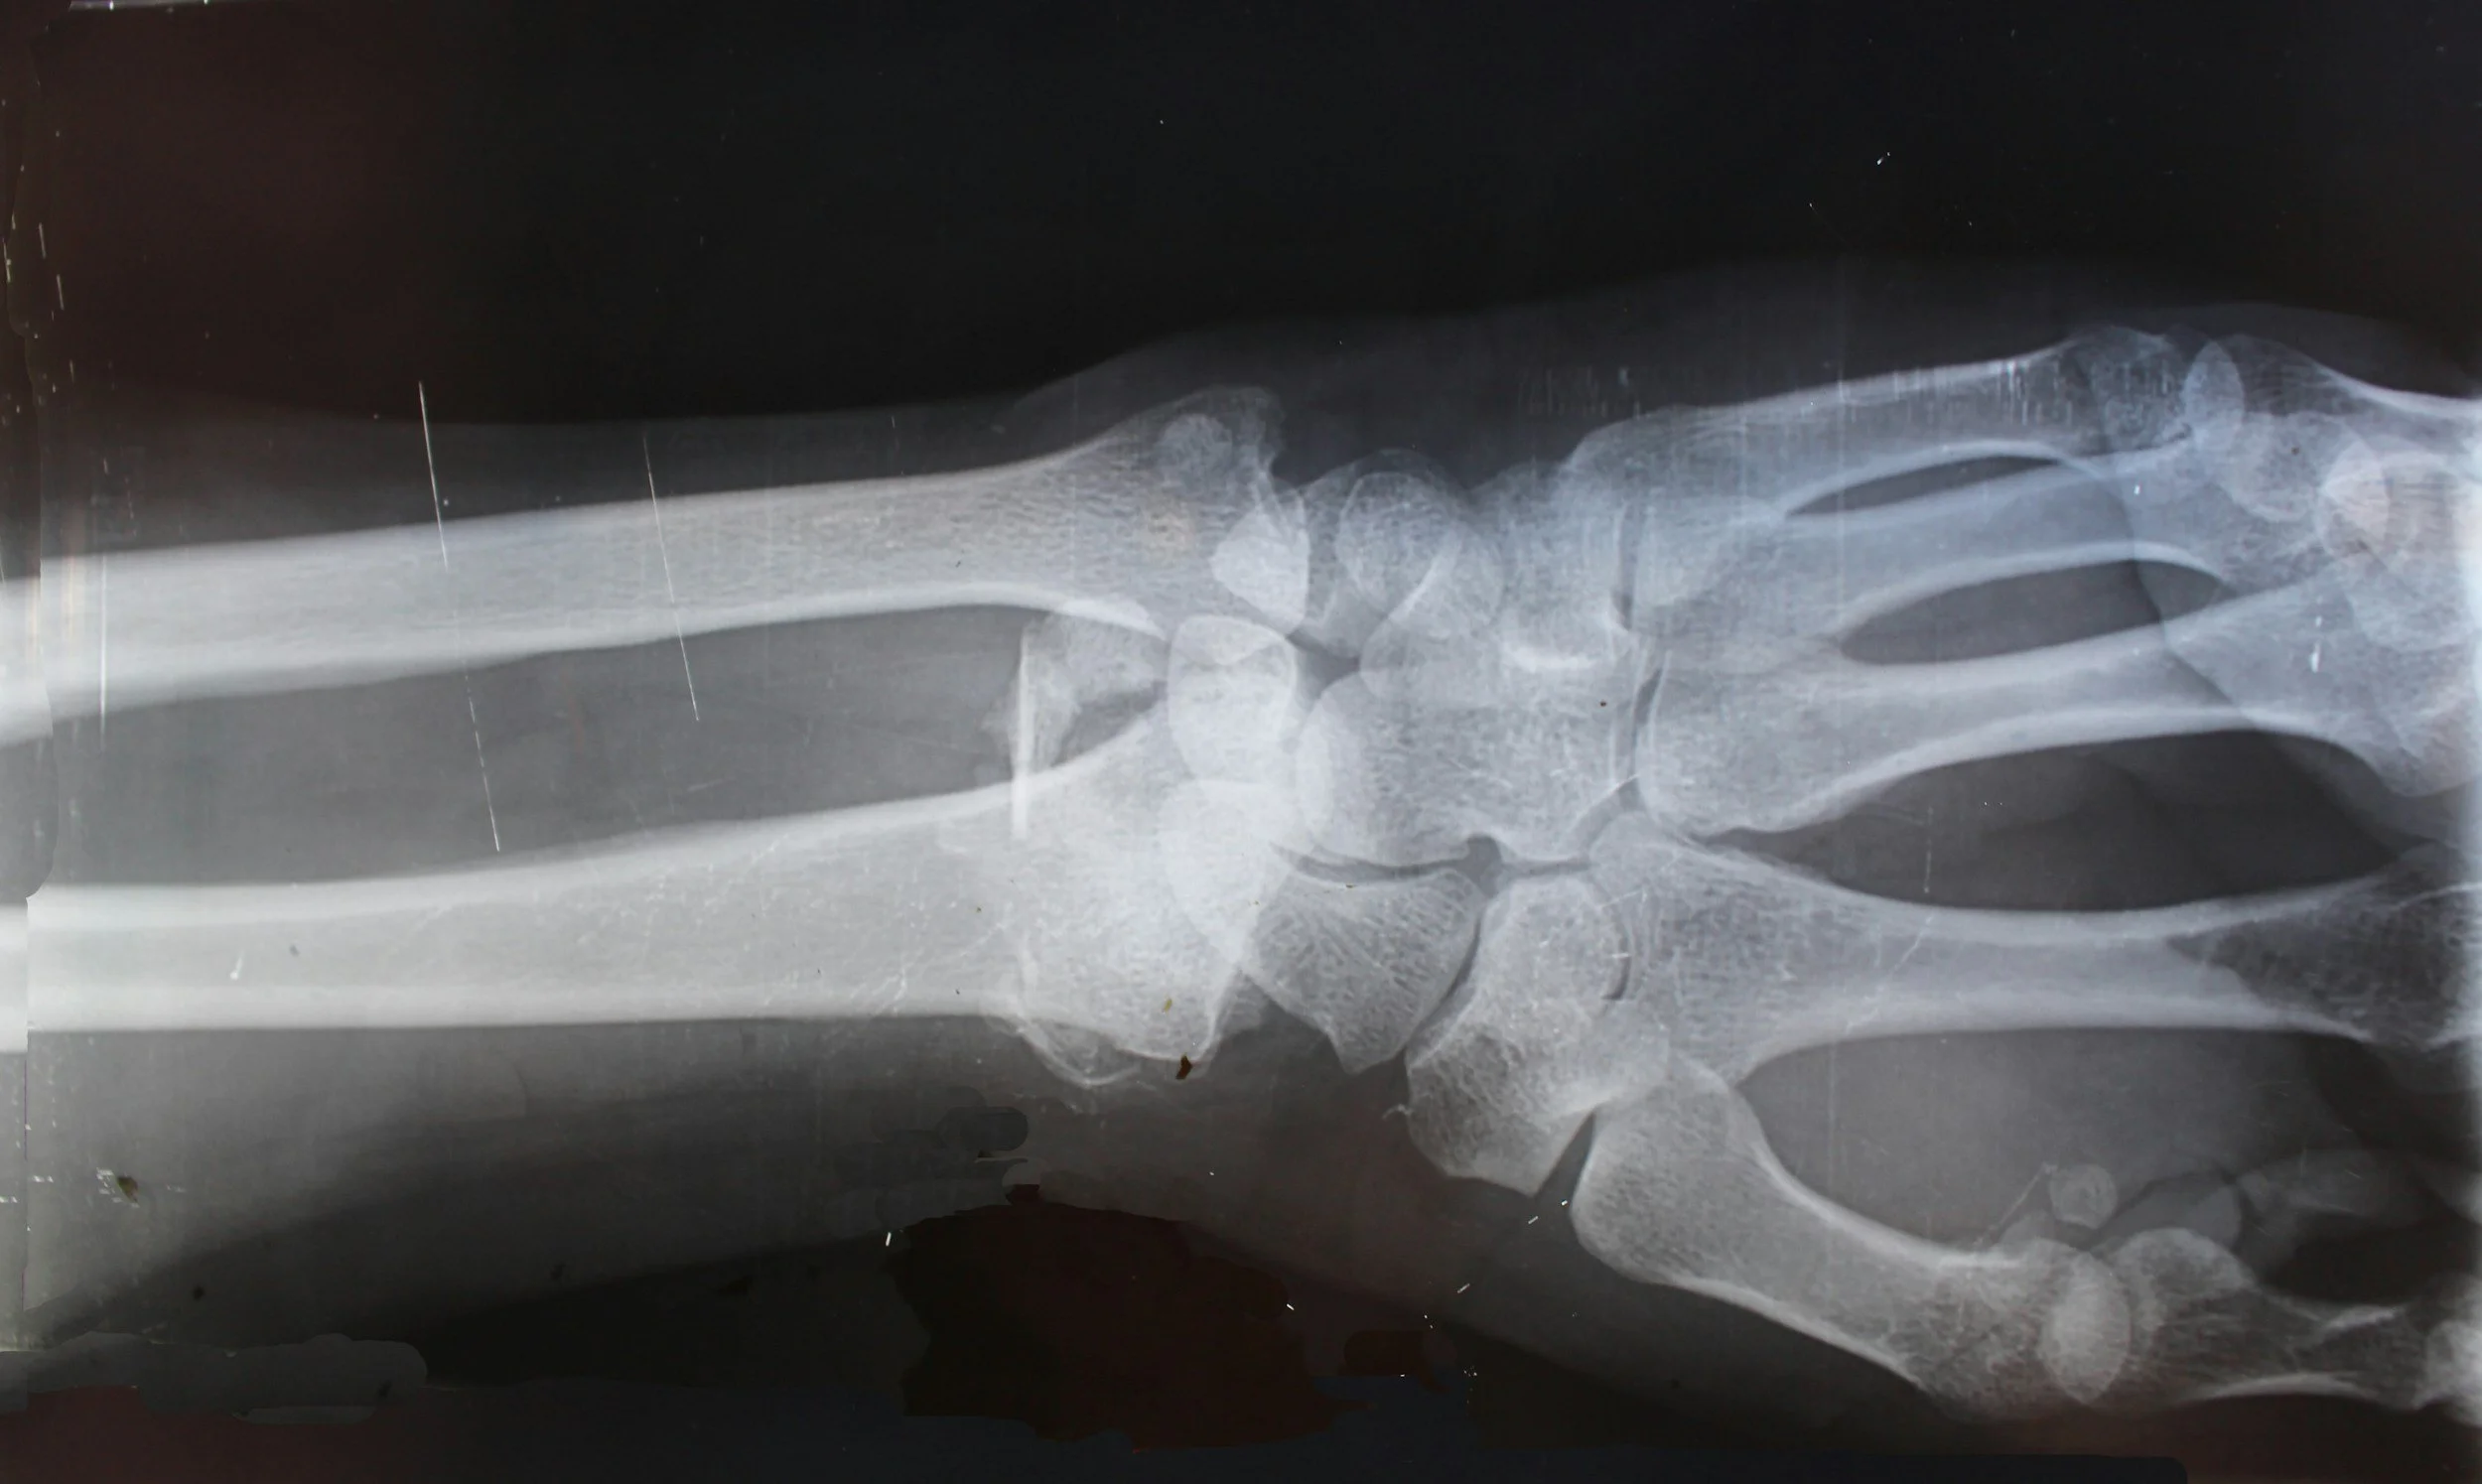

• X-Ray